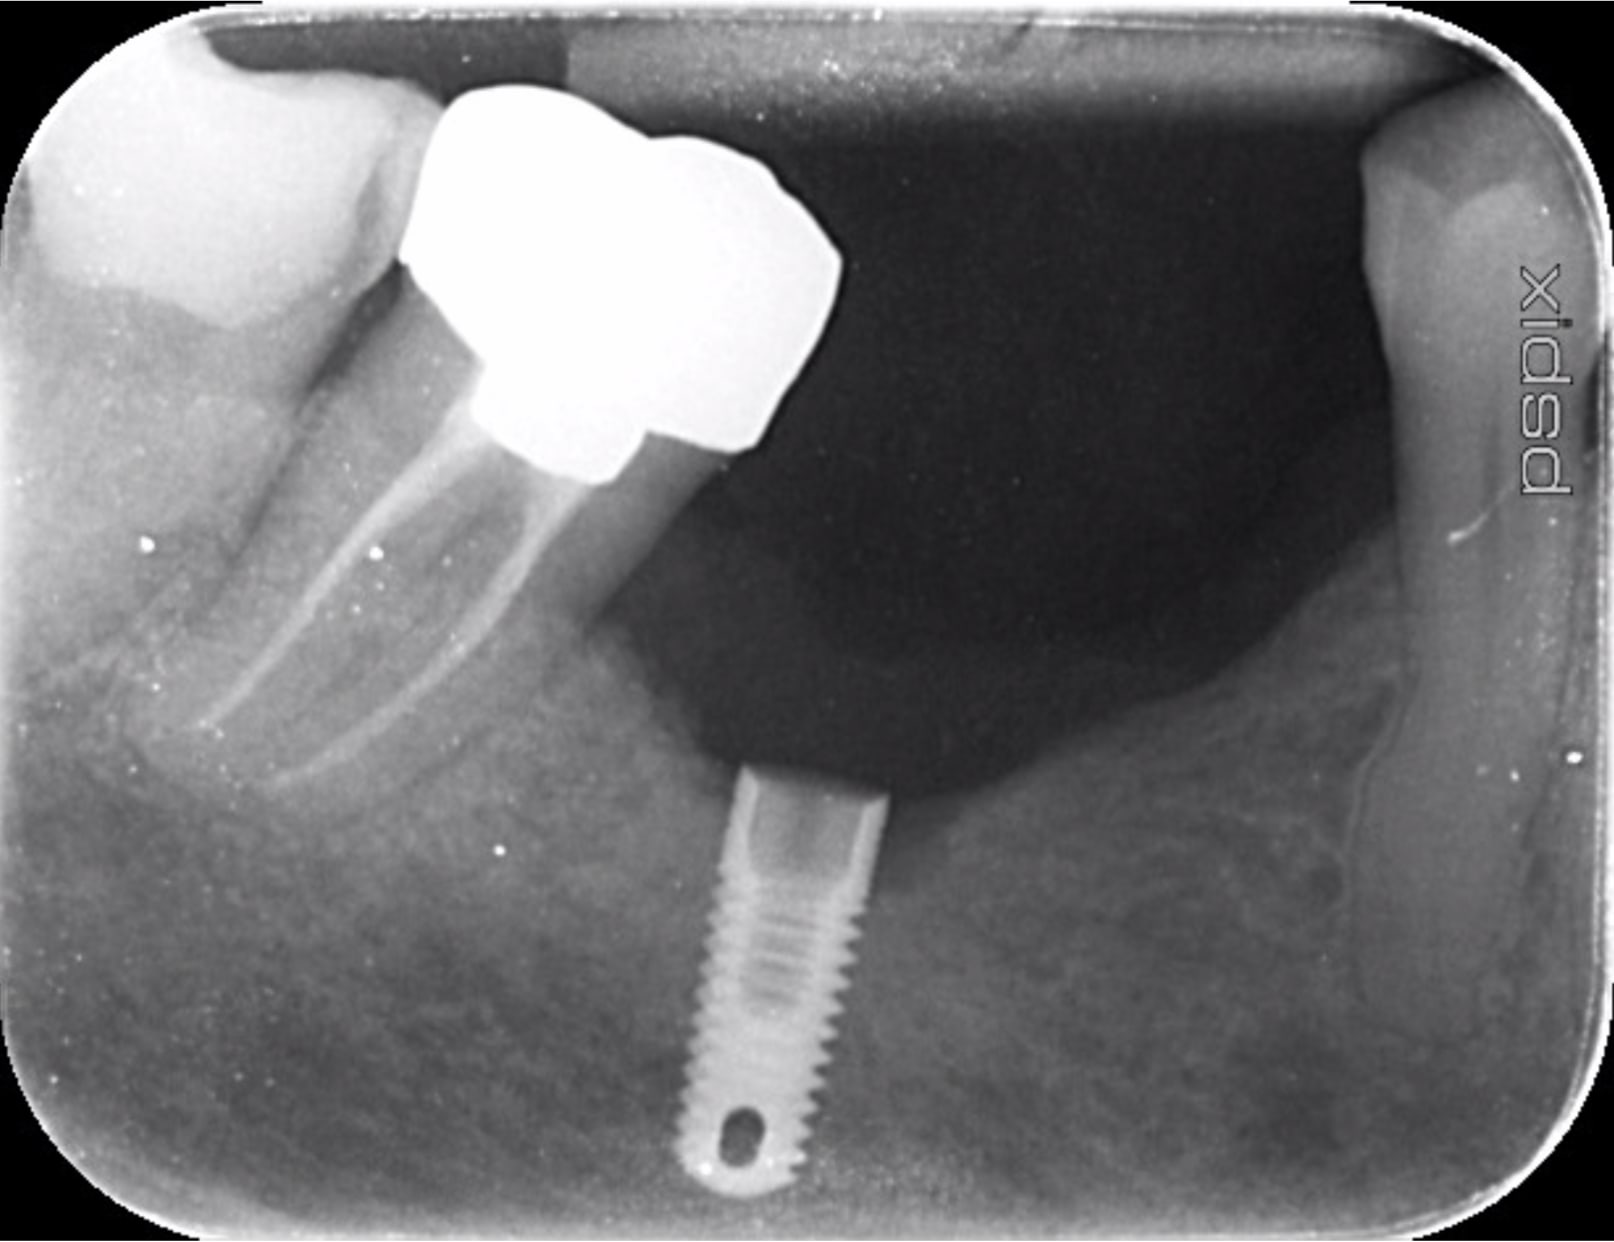

Un spécialiste pourrait m'aider à identifier cet implant ?

fastoche TSV Zimmer et c'est un 3.7mm donc plateforme 3.5mm